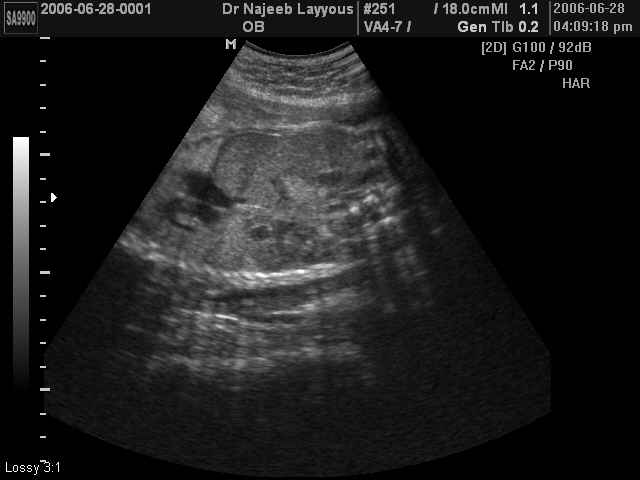

صور طبية للحمل بجهاز الالتراساوند | الدكتور نجيب ليوس